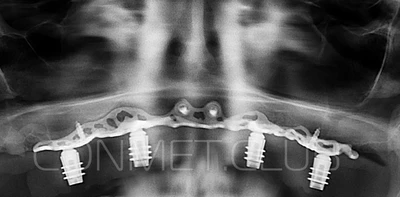

И в-четвертых: небольшой фрагмент из операции по восстановлению всех утраченных зубов на верхней челюсти. По сути эта операция полностью повторяет протокол и этапность операции представленной в первой части статьи, за исключением того, что искусственные зубы были зафиксированы сразу после операции. Со слов самой пациентки, процесс жевания был совершенно безболезненным с самого первого дня.

Клинические работы с субпериостальными имплантатами производства Конмет, проведенные в 2019 году, позволили унифицировать интерфейс данных имплантатов под современный цифровой протокол. Более того, необходимые конструкционные элементы были введены в официальную базу под программу Exocad. Что позволило сократить время изготовления зубного протеза до 1-3 дней!

2. После этого произвели компьютерное моделирование самого имплантата и фиксирующих элементов. Примечательно, что в абатментах, использовался отлично зарекомендовавший себя и проверенный десятилетиями интерфейс КОНМЕТ! В результате получили несколько специальных файлов, позволяющих не только сделать сам имлантат, но еще до операции изготовить и сами зубы. Данные файлы передали в изготовление на специальном 3D оборудовании.